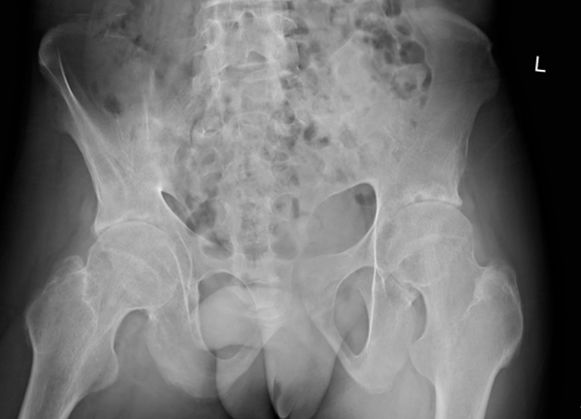

图:强直性脊柱炎伴轻度髋关节结构破坏改变

例1:21岁男性,AS患者,双髋关节疼痛伴活动受限4年